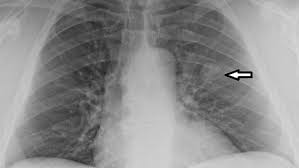

"폐결절(lung nodule)"은 폐 조직 내에서 직경 3cm 이하의 원형 또는 타원형 덩어리를 말합니다. 일반적으로 엑스레이나 CT 촬영에서 발견되며, 단독으로 존재하는 경우가 많지만 여러 개 나타날 수도 있습니다.

폐결절 진단은 주로 영상검사와 조직검사를 통해 이루어집니다.

- 영상 검사

- 흉부 X-ray: 초기 발견 용이, 해상도 낮음

- CT(컴퓨터단층촬영): 크기, 모양, 경계, 칼슘 침착 확인